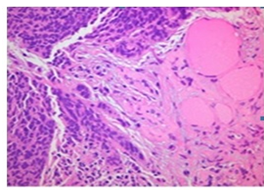

The patient was put into follow up for approximately one year. At first, biochemical relapse with increasing values of CA 125 was illustrated, while CT scans of chest and abdomen remained negative till 7/2016. The tumor marker CA 125 continued to increase (1680 U/ml) in August 2016, so we proceeded to a new PET-CT scan in 9/2016. There was pathological uptake in multiple mediastinal, cervical lymph nodes (SUV: 14), a thyroid lesion in the right lobe (SUV: 4) (Figure 1) and a hepatic lesion in segment IV (SUV: 3.5).

Figure 1 Thyroid metastasis on PET-CT.